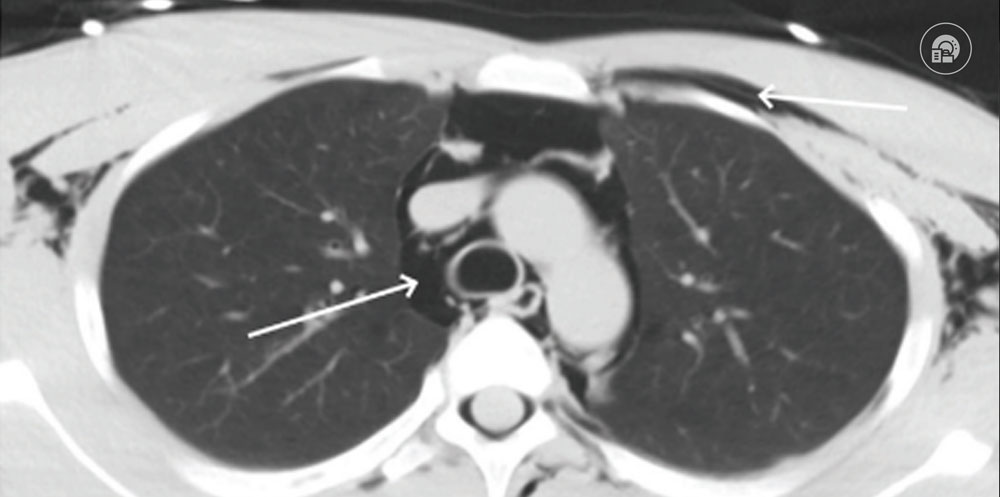

BİLGİSAYARLI TOMOGRAFİ

Travma hastalarının değerlendirilmesinde bilgisayarlı tomografi (BT) taramalarının kullanımı önemli ölçüde artmıştır. Göğüs röntgeni ile karşılaştırıldığında, göğüs BT’si:

- Pnömotoraks ve hemotoraksın tespitinde daha yüksek hassasiyete sahiptir.

- Göğüs kafesi, mediasten, akciğer parankimi ve aortu daha ayrıntılı değerlendirme imkanı sunar.

Künt Torasik Travmada BT Kullanımı

Künt toraks travması olan bir hastada BT çekme kararı, fiziksel bulgulara, yaralanma mekanizmasına ve klinik yargıya dayanmalıdır. NEXUS kriterlerine göre:

Gizli Pnömotoraks

Göğüs BT’sinde saptanan, ancak akciğer grafisinde görünmeyen pnömotoraks olarak tanımlanır.

- Travma hastalarının %2-10’unda rastlantısal olarak tespit edilir.